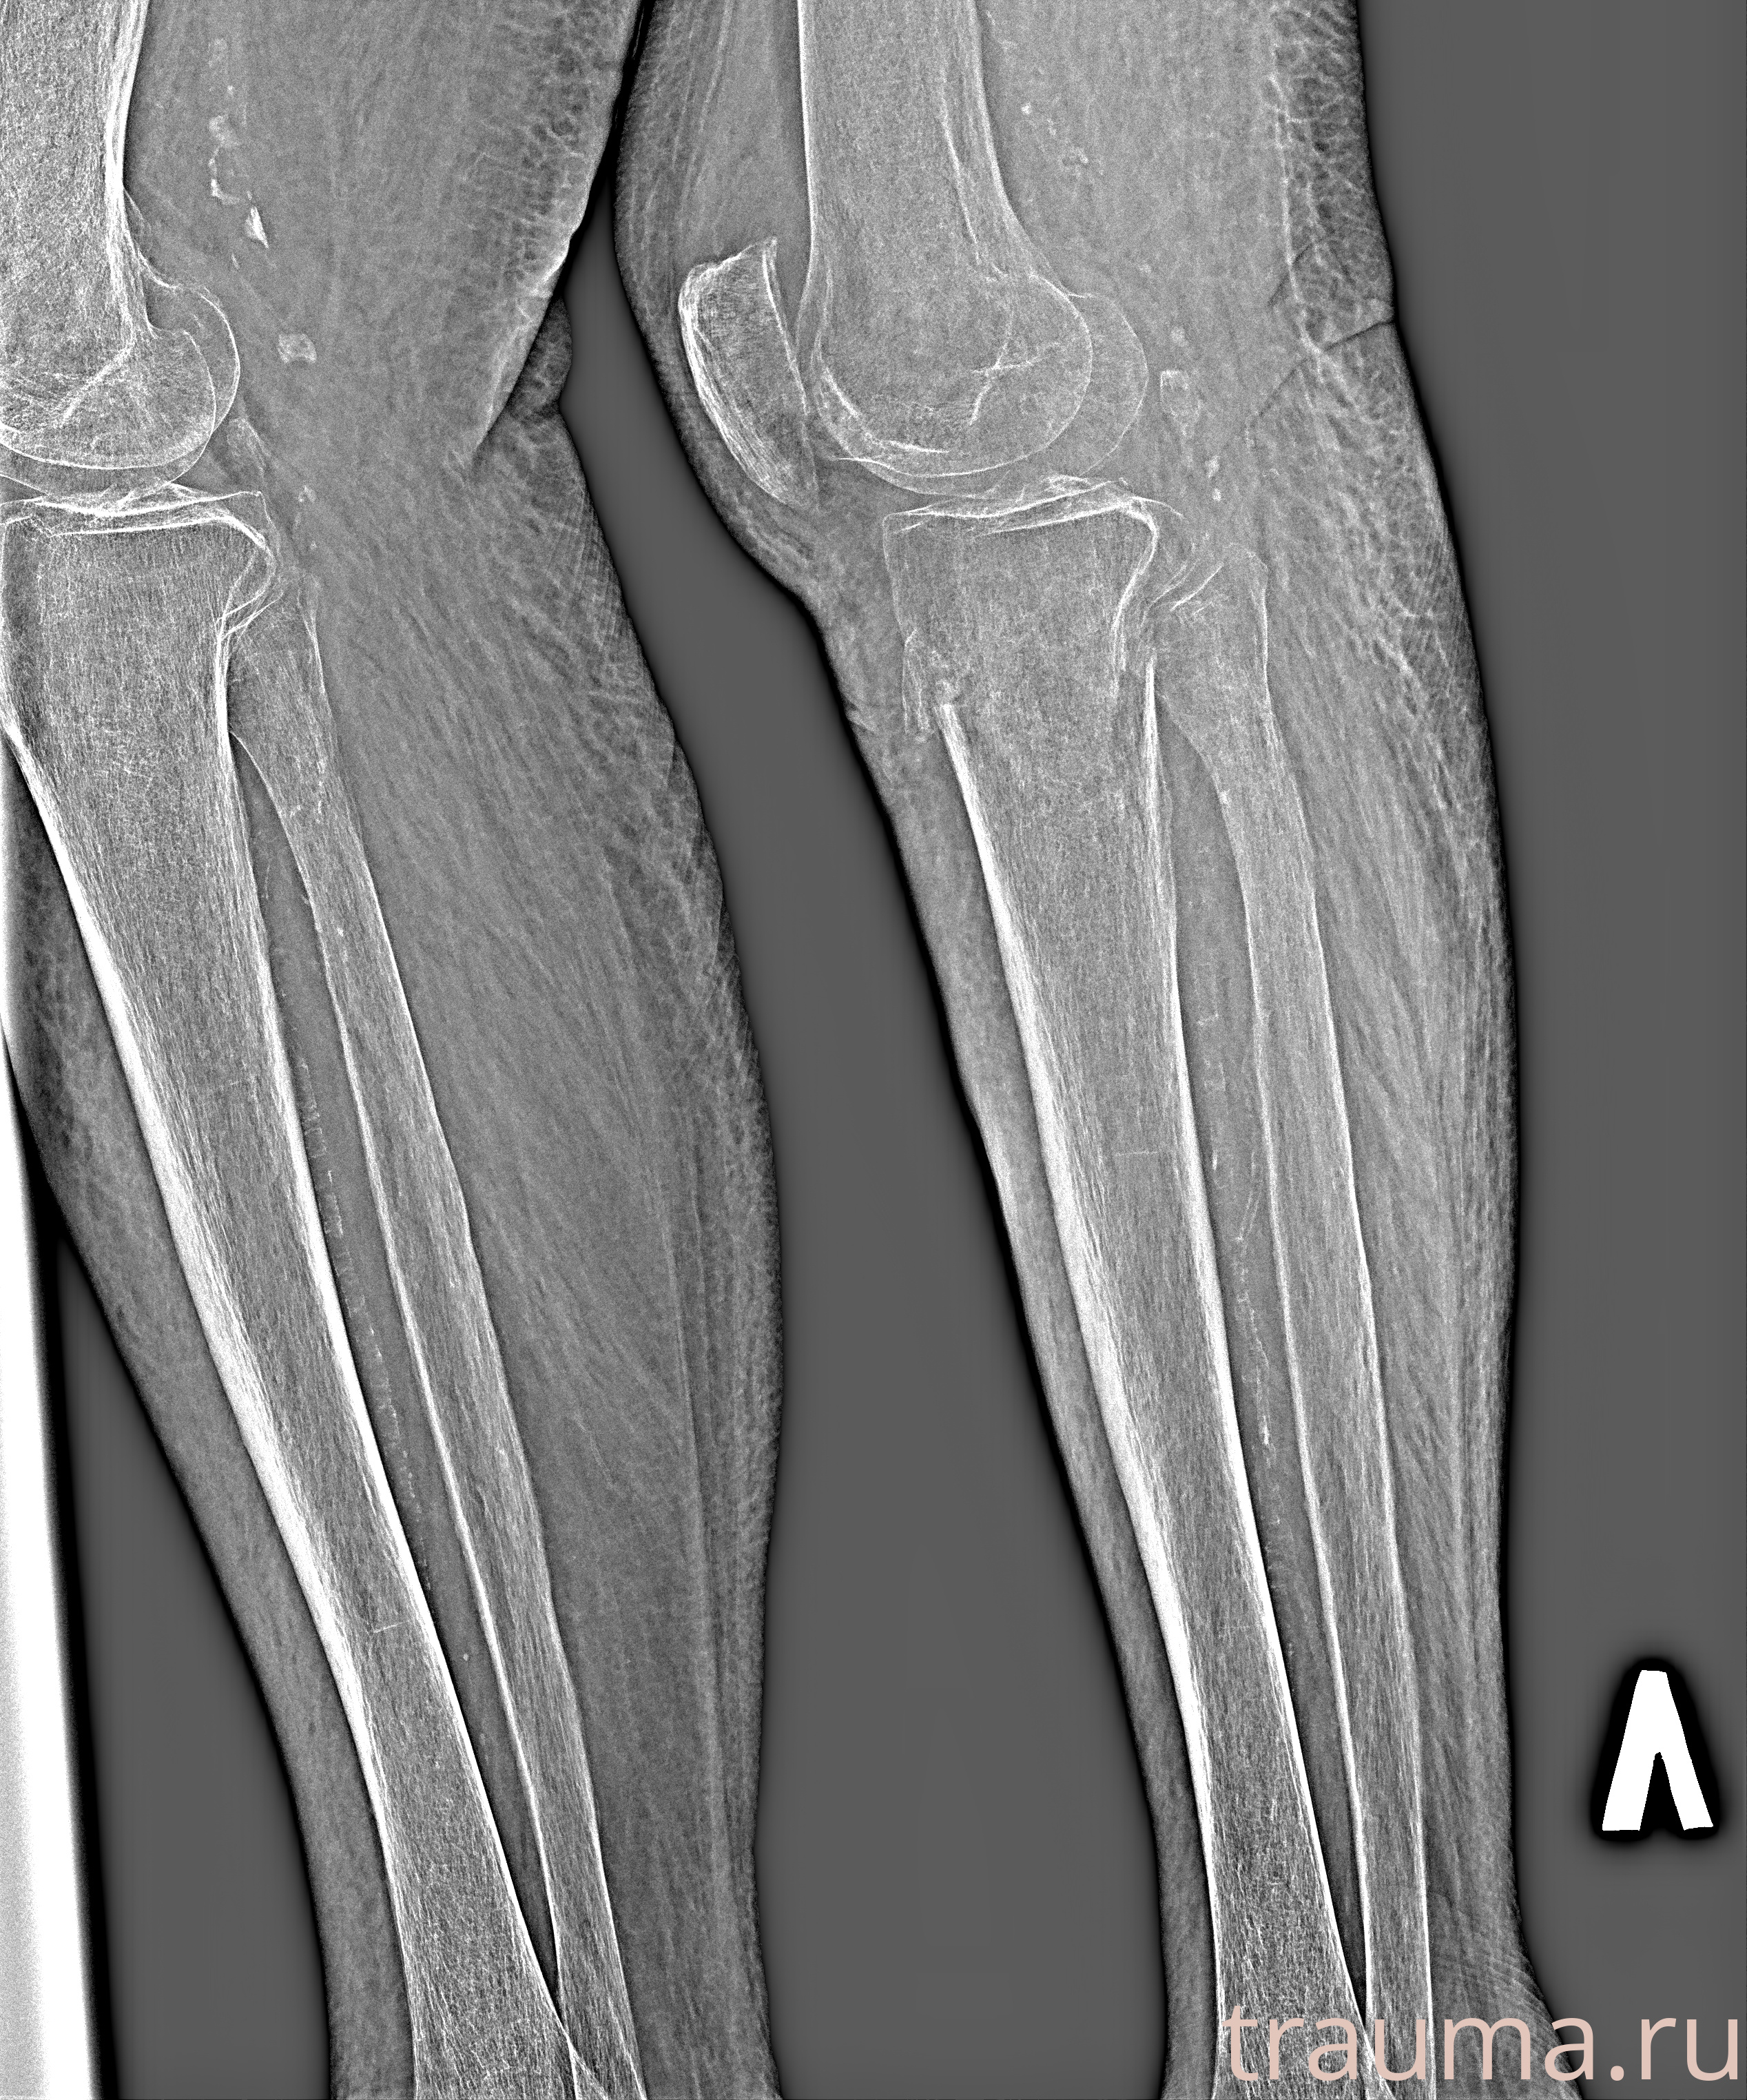

Рентген на дому: по вашему адресу приезжает врач-рентгенолог, травматолог-ортопед с мобильным рентгеновским аппаратом, проводит диагностику травмы или заболевания, делает необходимые рентгенограммы, дает рекомендации по дальнейшему лечению. Получить качественные снимки в домашних условиях возможно благодаря уникальной методике, разработанной МосРентген Центром для института  Склифосовского